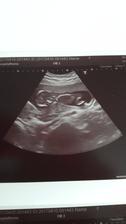

@sun89 Ahojky, trapi me otoky a vysoky tlak jak ten normalni tak i nitroocni, tak uvidime, jak budu/nebudu rodit. Jinak to bude chlapeček a jmeno vybrane už take mame❤😍❤ Jen jdu ted 26.9. znovu na ocni, co teda a jak😉 Manzel vcera prekvapil, ze chce jit k porodu, celou dobu nechtel a teď že ano🤔😎

@sun89 Jeee to mate super, u nas asi vitani obcanku nebude, maji to tak divne rozdelene, koukala jsem na to v porodnici a kdyz by bylo, tak az v unoru a jestli vubec😂Pak posli fotky, manzel kazdy den zacina otazkou:tak uz budes rodit?😂😂😂 Uz me s tim kazdy den tak trochu obtezuje😂 Tesi se hrozne moc a uz nemuze ani dospat😎🤔No uvidime, ja bych rada aby se maly narodil az v rijnu, jako ja a bracha a kdyby to vyslo na 10.10. coz je bracha, to by bylo slavy❤